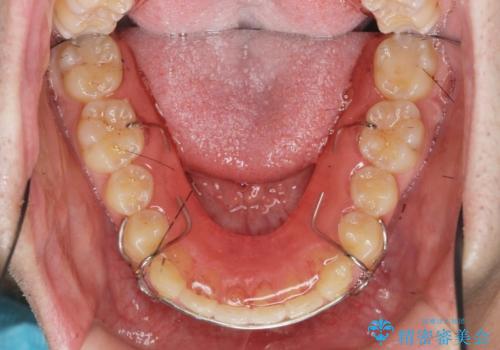

ガタつきの大きい前歯 インビザラインによるマウスピース矯正治療

- ガタつきの目立つ前歯の改善を求めて来院されました。

上顎前突、がたつきを改善すべく上顎臼歯の後方移動・ディスキングを行い歯並びの改善を計画します。

食事・歯ブラシ時以外の時間にしっかりとマウスピースを装着していただけたのでガタつきは大きく改善し良好な歯並びを得ることができました。